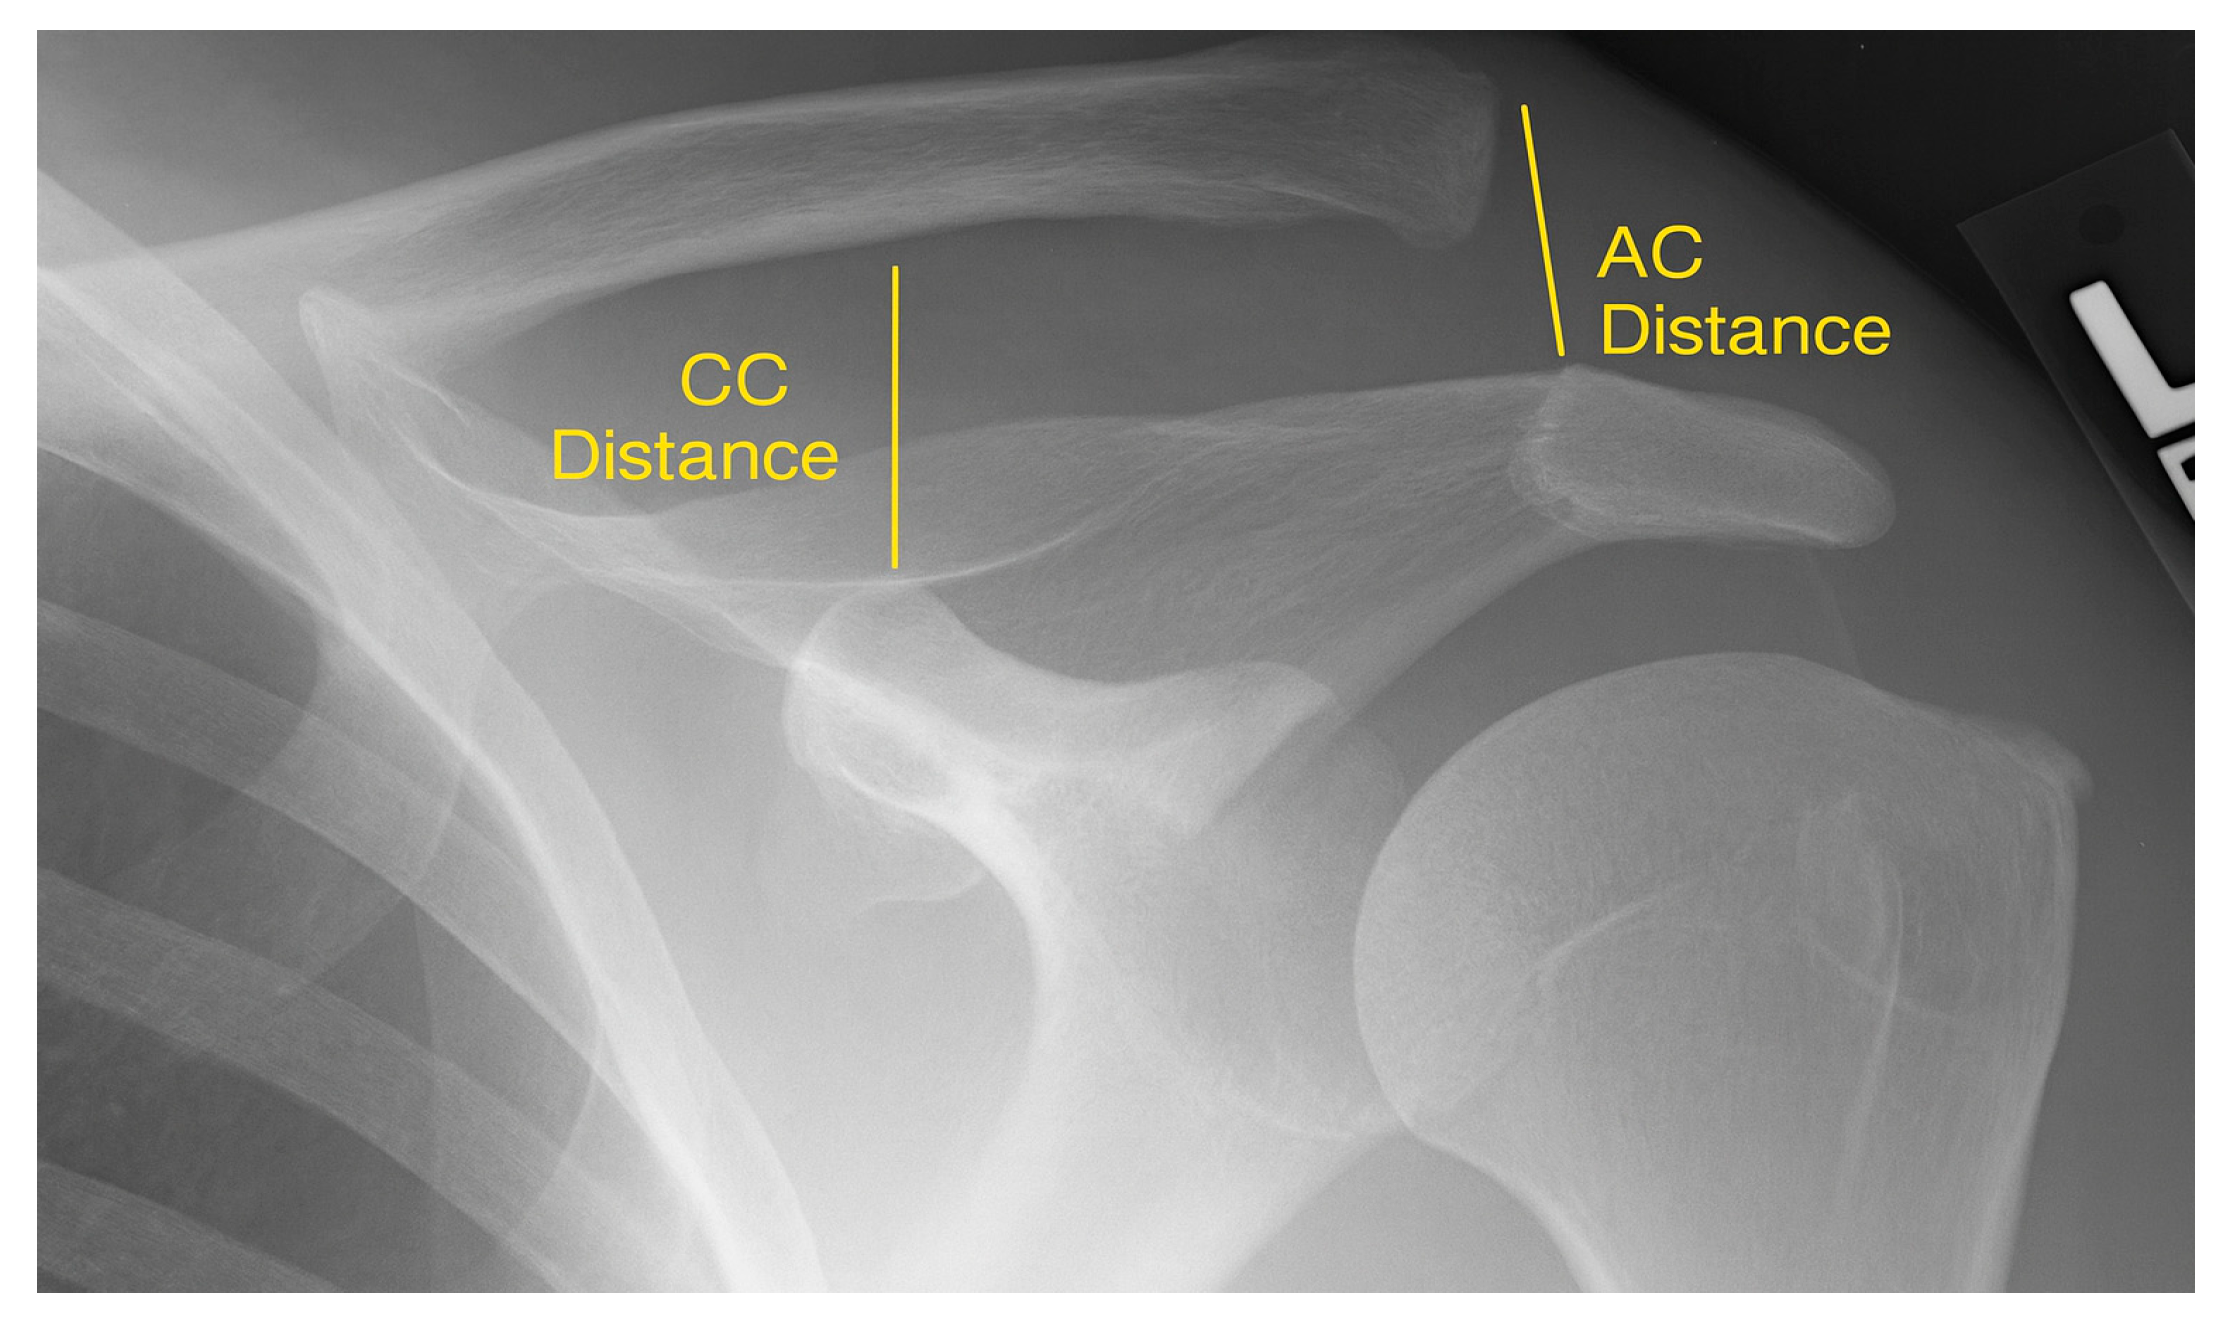

Standardized bilateral shoulder radiographs (anteroposterior, axial, and stress views) were obtained pre- and postoperatively. Stress images were taken with 5–10 kg weights in each hand. The primary radiographic parameters were the acromioclavicular (AC) distance—measured from the inferior acromion to the clavicle—and the coracoclavicular (CC) distance—from the superior coracoid process to the clavicle (Figure 1). Measurements were also taken from the contralateral shoulder for intra-individual comparison.

Figure 1.

Anteroposterior radiograph of the shoulder demonstrating measurement of the acromioclavicular (AC) distance and the coracoclavicular (CC) distance.